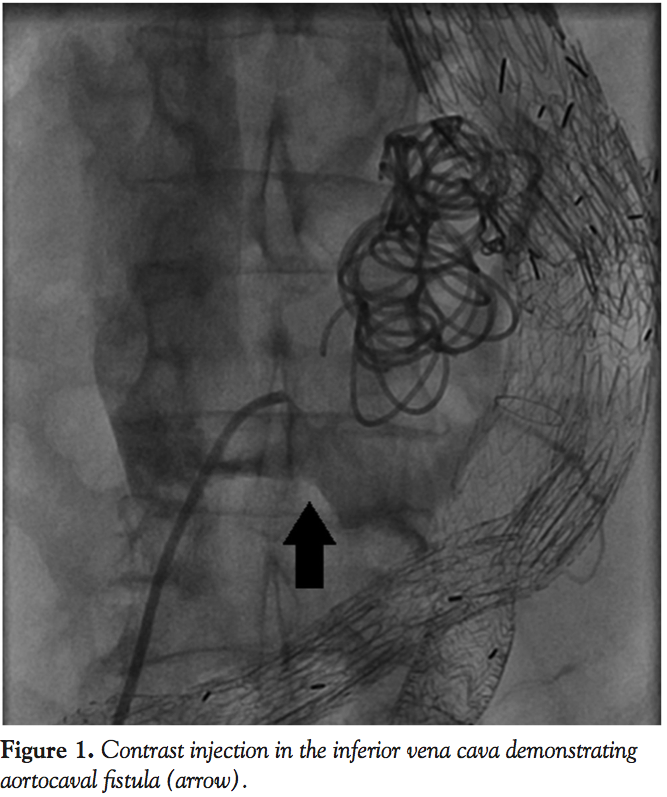

The follow-up CT scan on hospital day 9 demonstrated a large type 2 endoleak which communicated with the IVC through the aortocaval fistula. The flow through the aortocaval fistula was substantially reduced from prior study. Surgical closure of the aortocaval fistula was considered, but the patient was felt to be a high-risk operative candidate, and a percutaneous approach was pursued. On hospital day 13, the patient was taken to the cardiac catheterization lab and underwent coil embolization to the aneurysmal sac. Using fluoroscopic guidance, a 14-mm Amplatzer muscular ventricular septal defect (VSD) occluder device (AGA Medical, Plymouth, Minnesota) was successfully deployed across the aortocaval fistula (Figures 1 and 2). With contrast injection in the IVC, there was minimal opacification of the VSD occluder after deployment. Coil embolization of the inferior mesenteric artery was subsequently performed by interventional radiology, with resolution of the Type 2 Endoleak. Follow-up CT scan revealed no evidence of endoleak, and stable position of the VSD occluder device with no flow visualized across the aortocaval fistula. The patient was discharged to a rehabilitation facility for physical therapy.